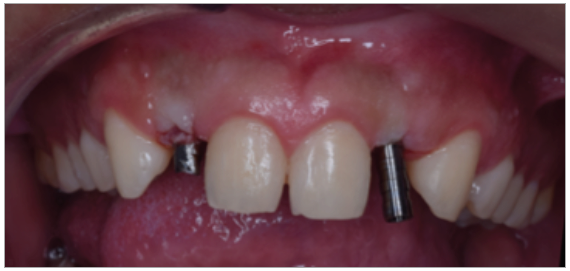

Paciente de sexo masculino de 24 años de edad, de raza mestiza, sin antecedentes sistémicos y oclusalmente estable, que fue transferido al servicio de Rehabilitación Oral del Posgrado y Especialización de la Universidad Peruana Cayetano Heredia, Lima, Perú. Recibió previamente tratamiento ortodóncico en el servicio de Ortodoncia y Ortopedia Maxilar por 6 años. Al examen intraoral presentó agenesia de las piezas 12 y 22 con evidencia de defectos óseos, presenta fenotipo periodontal grueso (figura 1). Al examen radiográfico se observa disminución generalizada de las raíces (Rizomicri), presenta ensanchamiento del ligamento periodontal generalizado (figura 2). Para el plan de trabajo para el diagnóstico se obtuvieron modelos de estudio primario, realizando el encerado para la planificación del tratamiento del sector anterosuperior. Al análisis tomográfico se evidenció poca disponibilidad ósea, motivo por el cual se planificó dos injertos en bloque de mentón con hueso particulado y plasma rico en plaquetas previo a la colocación de implantes dentales (figura 3 y figura 4). Pasado el tiempo de osteointegración (6 meses) se colocaron dos implantes Strong WS Cono Morse (SIN®, Sao Paulo, Brasil) de 3.5 mm x 11 mm. En la segunda fase, se confeccionaron provisionales de acrilico termocurado Vitalloy® (Vitacryl; A. Tarrillo Barba S.A., Lima, Perú) para el manejo de los tejidos blandos a nivel de las piezas 12 y 22, los cuales estuvieron fijados a un cilindro provisional de titanio (SIN®, Sao Paulo, Brasil) atornillado al implante, verificando la adaptación de este al implante mediante una radiografía periapical (figura 5). El cilindro fue recortado dando una altura de 6 mm, los provisionales fueron agujerados en el medio (figura 6), de tal forma que el cilindro calce en el medio del espacio edéntulo, se cubrió la entrada del cilindro con teflón (Golfo USA®) y se capturó el cilindro con acrílico de autocurado Duralay color 62 (Reliance Dental Manufacturing LLC, Illinois USA) (figura 7). Después del acrilizado se retiró el provisional, en la parte cervical se realizó un incrementó con resina fluida (Filtek™ Z350XT Flow - 3M ESPE Dental Products. St. Paul, Minnesota, USA) formando el contorno crítico a 2mm por debajo del zenit de los incisivos centrales de tal manera que entre los zenits de los incisivos centrales, laterales y caninos formen una zona triangular. El contorno subcrítico se realizó de forma convexa (figura 7 y figura 8). Se finalizó con el acabado y pulido del provisional con gomas de grano grueso (gris) y grano fino (verde) (Politip, Ivoclar-Vivadent; Schaan, Liechtenstein). Se manejó la conformación de los tejidos blandos en 2 citas mediante la adición por capas de resina compuesta (Filtek™ Z350 - 3M ESPE Dental Products. St. Paul, Minnesota, USA) a nivel del contorno crítico y subcrítico a las 2 semanas y 4 semanas de la instalación del provisional (figura 9 y figura 10). Se logró conformar las papilas interdentales, el contorno crítico y subcrítico observando que los tejidos se encontraran estables, sin inflamación, con el color de la encía igual a la encía adyacente; todo esto nos indicó que se podía realizar la impresión definitiva. La instalación final se realizó con coronas metal cerámicas cementadas (figura 11 y figura 12).